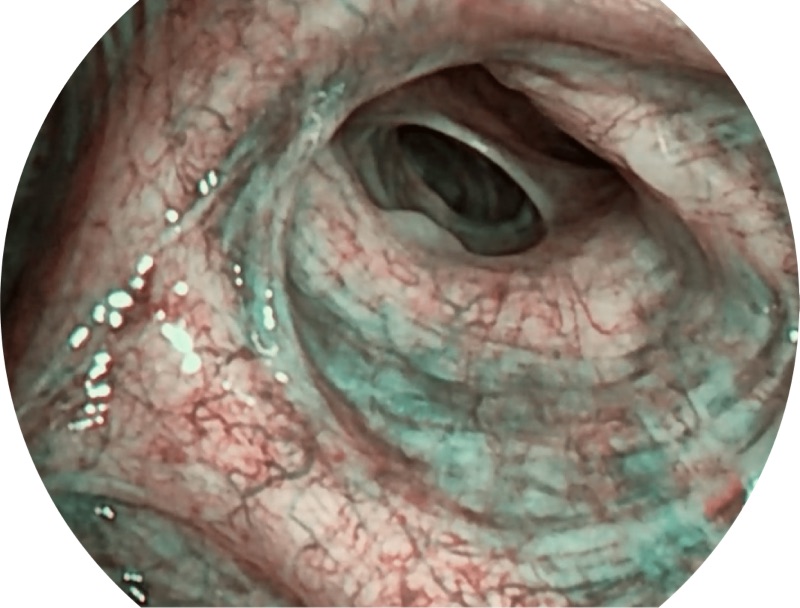

VIST